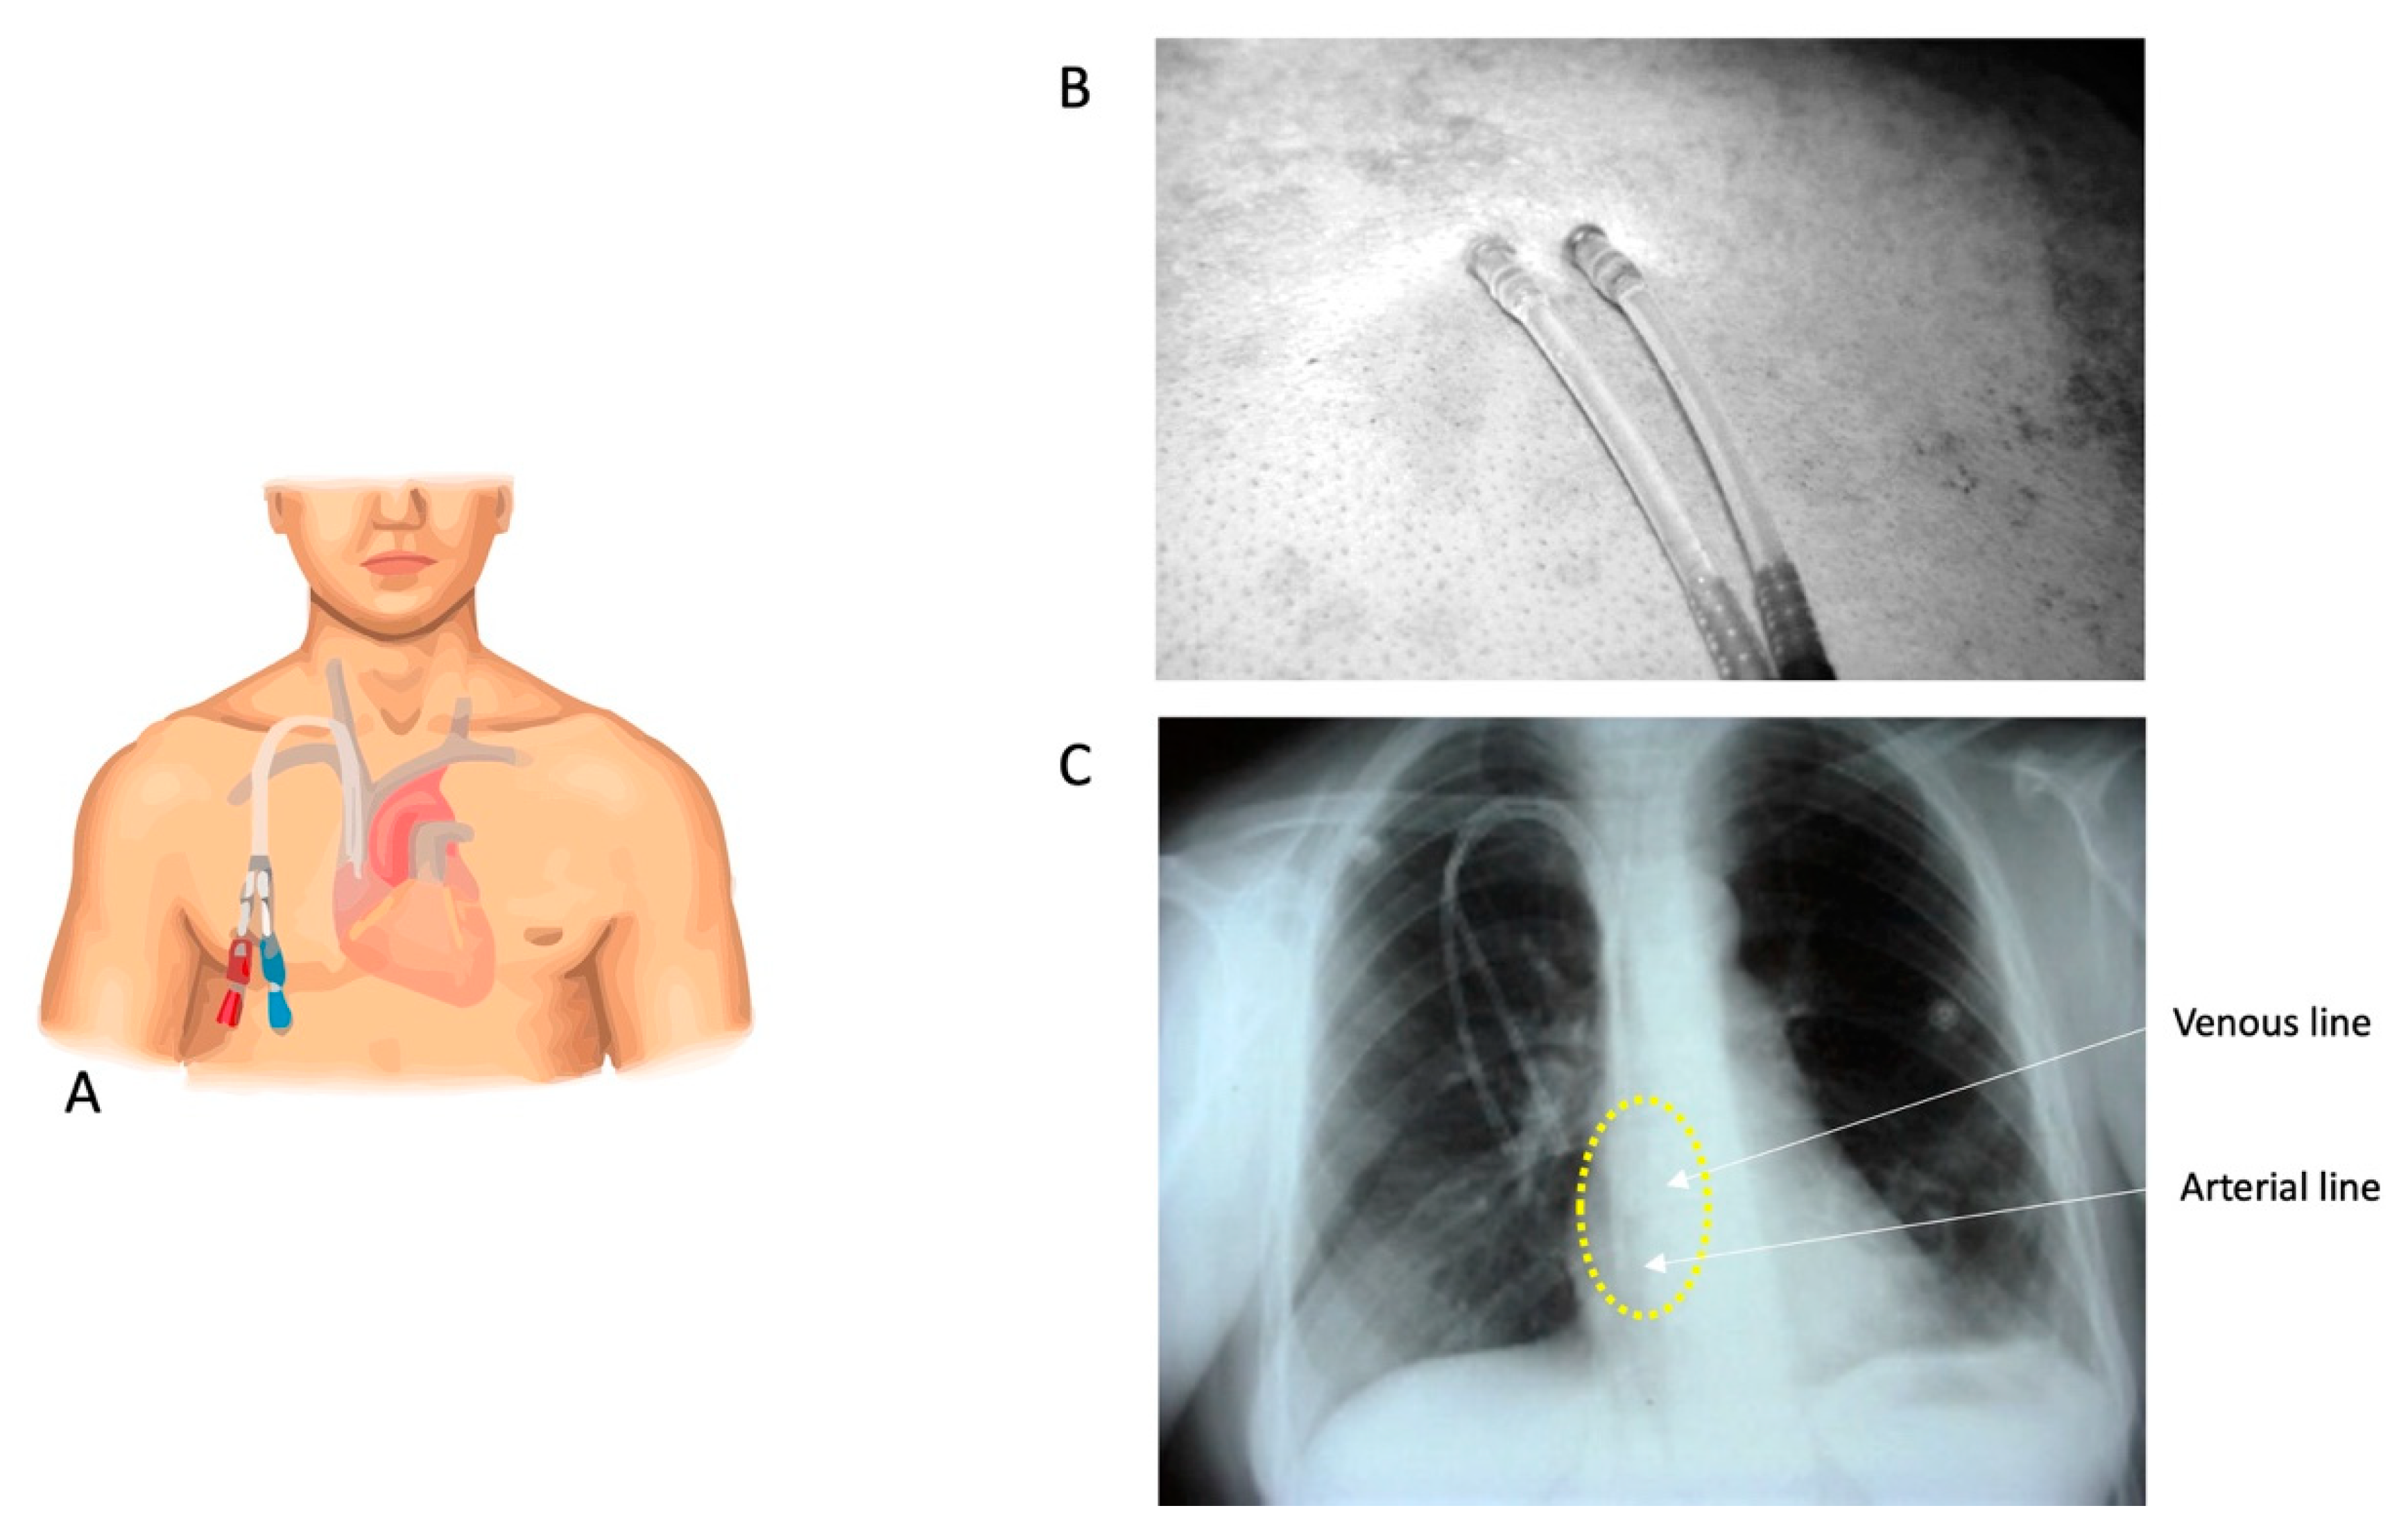

2.4.1. DualCath Looking and Imaging (Figure 1)

- Canaud, B.; Leray-Moragues, H.; Klouche, K.; Morena-Carrere, M.; Chenine, L.; Miller, G.; Cristol, J.P.; Canaud, L. Percutaneous Placement and Management of High-flow Catheter for Hemodialysis: The case for DualCath, two tunneled single lumen silicone catheters. J. Vasc. Access. 2023. [Google Scholar]